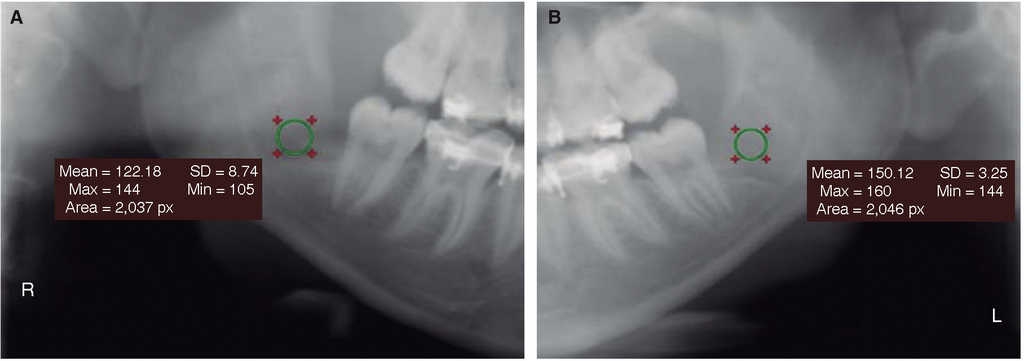

Se observó al octavo día si las heridas estaban abiertas o cerradas (Figura 2). A los 60 días se tomó la radiografía panorámica digital (I-Max Touch 3d Owandy Radiology), la misma que fue procesada en el software RadiAnt DICOM Viewer Versión 2.2.9.10728 mediante la herramienta Ellipse; éste es un software de uso médico odontológico que cuantifica la densidad de contraste imagenológico con la media de valor de píxel o unidades Hounsfield para imágenes de tomografía axial computarizada (Figura 3).16

La cicatrización del tejido óseo tuvo mejor puntuación en el lado experimental con valores de densidad de 163.9 HU comparado con el lado control de 159.3 HU (Figura 7). La prueba t de Student dio un resultado de p = 0.015. Con relación al sexo y edad no se obtuvieron diferencias (Cuadro I). De acuerdo con la propuesta de criterios y escala de puntuaciones de Pederson, con relación a la dificultad de extracción, los mejores resultados se obtuvieron para los grupos de leve complejidad de extracción (Figura 8).